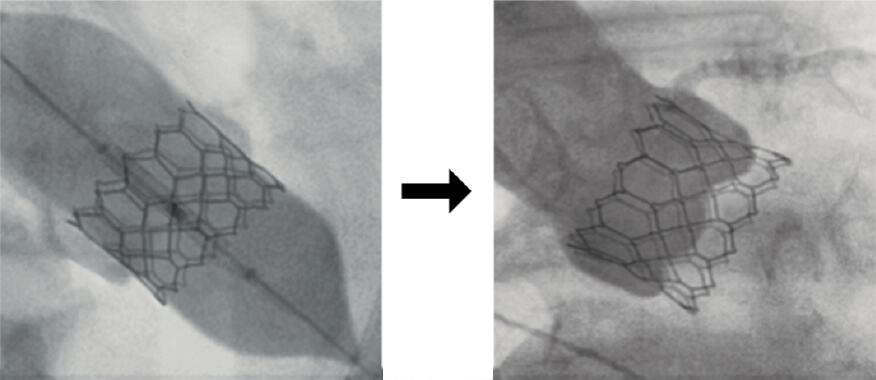

MitraClip®とは、カテーテルを用いて合いが悪くなっている僧帽弁をクリップで引き寄せ、逆流を減らす治療です。外科的な僧帽弁形成術や置換術と異なる点として傷はカテーテルが挿入される足の付け根のみであること、高齢であったり手術リスクが高い方でも施行可能であること、カテーテルを使用するため術後早期(翌日)からリハビリテーションが可能である一方で、完全に逆流を無くすのは難しいことなどがあります。患者さんの状態に応じて治療法は外科的な僧帽弁形成術や置換術が望ましいことや、MitraClip®が望ましいことがあります。僧帽弁閉鎖不全症があると言われたけれど治療法について質問がある、そもそも治療すべきかどうかわからないなどありましたら、まずは受診してみてください。

(Abbott社より提供)